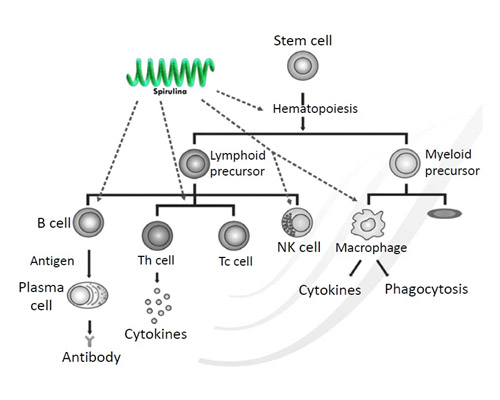

Spirulina as Immunity Enhancer

| ANTIBODY RESPONSE AND MACROPHAGE | |||||||

| Spirulina enhances hematopoiesis to produce more erythrocytes and lymphocytes | |||||||

| Spirulina shows direct effect on innate immunity by activating macrophages and NK cells | |||||||

| Spirulina activates T-helper cells and T-cytotoxic cells | |||||||

| Spirulina induces the maturity of B-cells for the production of antibodies | |||||||

| MUCOSAL IgA RESPONSE | |||||||

| Agglutination of micro-organisms | |||||||

| Neutralization of bacterial enzymes, toxins, and viruses; immune exclusion | |||||||

| Blocking adherence of bacteria to the epithelium | |||||||

| Reduction of antigens or allergen absorption. | |||||||